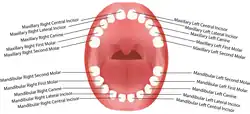

In dentistry, the crown is the visible part of the tooth above the gingival margin and is an essential component of dental anatomy. Covered by enamel, the crown plays a crucial role in cutting, tearing, and grinding food. Its shape and structure vary depending on the type and function of the tooth (incisors, canines, premolars, or molars), and differ between primary dentition and permanent dentition. The crown also contributes to facial aesthetics, speech, and oral health.

The surface of the tooth that faces the lips or cheeks is referred to as the facial surface. In anterior teeth, such as incisors and canines, this surface is more specifically known as the labial surface, while in posterior teeth, such as premolars and molars, it is termed the buccal surface.[1]

The lingual surface is the side of the tooth that faces the tongue. In the upper jaw or maxillary arch, this surface may also be referred to as the palatal surface due to its proximity to the palate.[1]

The occlusal surface is the chewing surface found on posterior teeth (premolar and molars), whereas anterior teeth have an incisal edge, which is a sharp cutting edge used for biting.[1]

The sides of a tooth that make contact with neighbouring teeth are called proximal surfaces. If the surface faces toward the midline of the dental arch, it is known as the mesial surface. Conversely, if it faces away from the midline, it is termed the distal surface.[1]

The crown contributes to multiple functions, including mastication, speech, aesthetics, and protection of supporting oral structures. Incisors, positioned at the front of the mouth, have sharp edges for cutting food and aiding in speech. Canines have pointed cusps to tear food and support the bite. Premolars combine tearing and grinding functions, while molars, with their broad surfaces, are specialised for crushing and grinding food.[2]

Incisors

In the permanent dentition, maxillary central incisors have broad, rectangular crowns with a straight incisal edge. Newly erupted incisors often display three mamelons, which wear down with time. The lingual surface contains a distinct cingulum bordered by mesial distal marginal ridges, enclosing a shallow lingual fossa.[12] Maxillary lateral incisors are smaller, with rounded incisal angles and a deeper lingual fossa that may include developmental grooves.[12] Mandibular central incisors are the smallest teeth and exhibit a symmetrical crown with a straight incisal edge and smooth lingual surface. Mandibular lateral incisors are slightly larger and possess a distally sloping incisal edge.[12][14]

Canines

Permanent maxillary canines are characterised by a prominent labial ridge, a well-developed cingulum, and a pronounced pointed cusp. The crown appears diamond-shaped from the incisal view, with strong mesial and distal slopes. The lingual anatomy includes a central ridge flanked by shallow fossae and prominent marginal ridges.[12][16] Mandibular canines are narrower mesiodistally, with a less prominent cingulum and smoother lingual surface. Their crowns are generally flatter and less pointed than those of maxillary canines.[16]

Premolars

Maxillary premolars usually have two cusps–buccal and lingual. The first premolars show sharp buccal cusp and a smaller lingual cusp separated by a central groove. They often exhibit a pronounced buccal ridge and occlusal sulcus.[12][13] The second premolars are smaller with cusps of more equal height and display more supplemental grooves on the occlusal surface.

Mandibular first premolars have a dominant buccal cusp and a much smaller lingual cusp, often giving the appearance of a single cusp. The crown tapers sharply towards the lingual side.[13] Second premolars typically have two lingual cusps and a broader, square, or round occlusal table. Their occlusal groove pattern may vary from Y, H, to U shapes.[13]

Molars

Maxillary first permanent molars have four main cusps, and sometimes a fifth cusp known as the cusp of Carabelli. The occlusal surface typically has a rhomboidal shape and includes a distinct oblique ridge connecting the mesiopalatal and distobuccal cusps.[12] Second maxillary molars are smaller, and the distopalatal cusp may be reduced or absent, giving rise to a heart-shaped occlusal form. Third molars are highly variable in anatomy, often smaller and more rounded, with numerous accessory grooves and ridges.[12]

Mandibular first molars have five cusps and a pentagonal occlusal outline. They include three buccal and two lingual cusps, separated by distinct grooves. The mesiobuccal cusp is typically the largest.[17] Second molars have four cusps of nearly equal size and a rectangular occlusal outline, with grooves forming a cross pattern. Third molars exhibit significant anatomical variation and often have wrinkled occlusal surfaces due to supplemental grooves.[12]